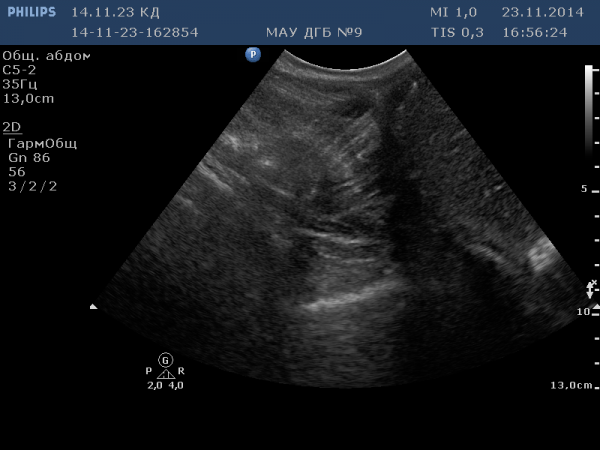

1 - симптом горнолыжника:

пример №1: с. горнолыжника - больше ассоциативный симптом, чем реальный = поперечный срез полового члена.